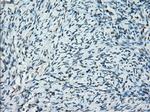

PRKY Monoclonal Antibody (OTI3E10), TrueMAB™

A group of proteins that are intimately involved in this process are the serine/ threonine (Ser/Thr) protein kinases. PRKY (protein kinase, Y-linked) and PRKX (protein kinase, X-linked) are members of the Ser/Thr protein kinase family, both of which belong to the subfamily of cAMP-dependent kinases. Encoded by a gene that is located near the pseudoautosomal region on chromosome Y, PRKY contains one protein kinase domain through which it catalyzes the ATP-dependent phosphorylation of target proteins. Functioning in a similar manner to PRXY, PRKX contains one protein kinase domain and is essential for macrophage differentiation and renal epithelial cell migration. Defects in the genes encoding PRKY and PRXX are associated with sex reversal disorder, namely XX in males and XY in females.